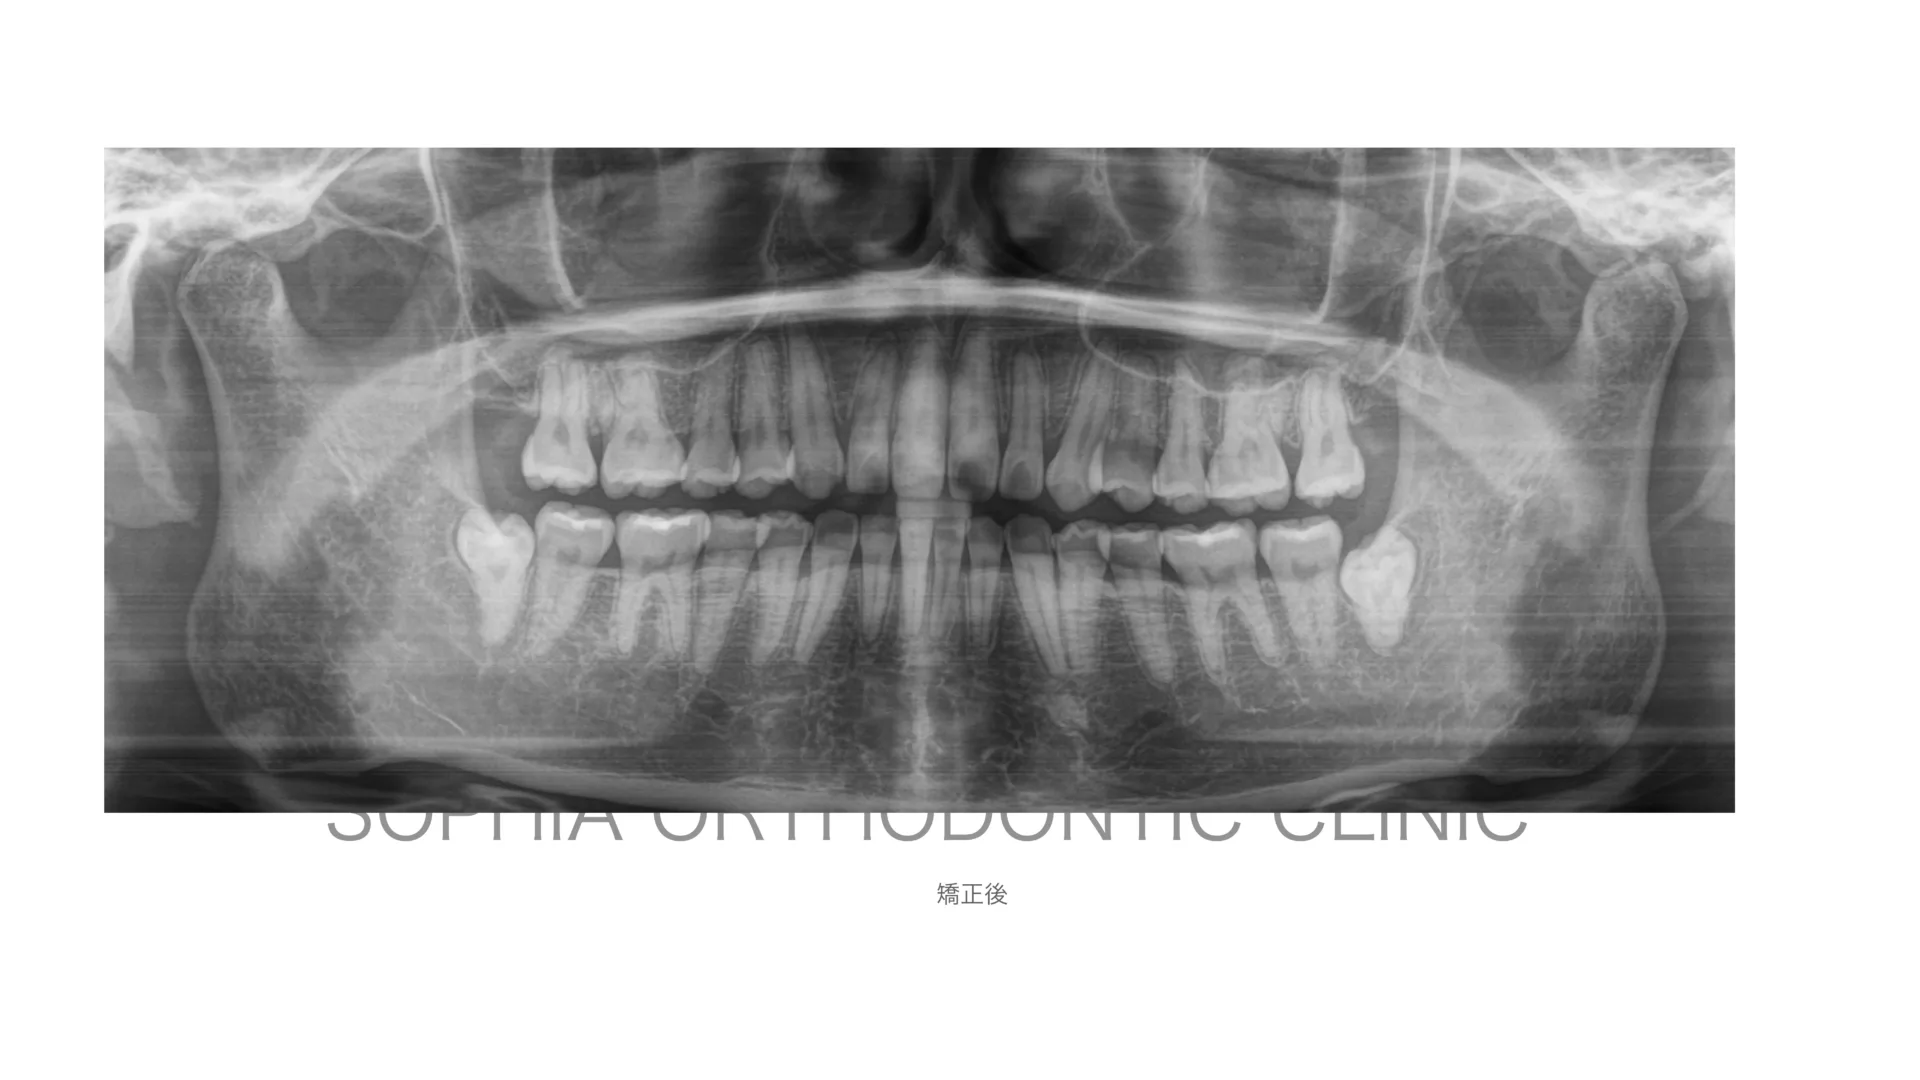

開咬症例 非抜歯 唇側